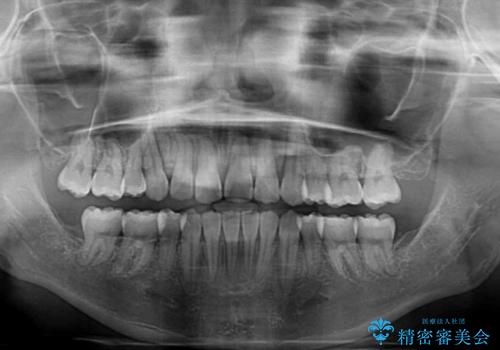

- 抜歯矯正の後戻りを気にして来院された患者様です。

舌の突出癖によるオープンバイトになっていたため、インビザラインによるマウスピース矯正をおすすめしましたが、自己管理の自信がないとのことで、ワイヤー装置による矯正治療を行うこととしました。

舌の突出癖が認められると、上下前歯の隙間を閉じることができません。

舌のトレーニングをしっかりと行っていただくことで、歯列を整えることができます。